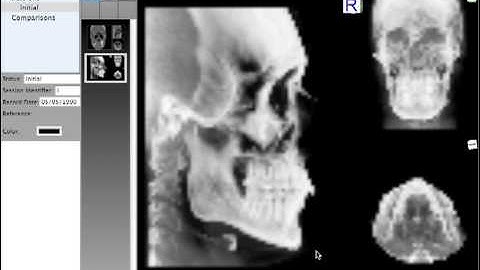

Quick Ceph Studio - Extracing Condyle Views from CT Scan